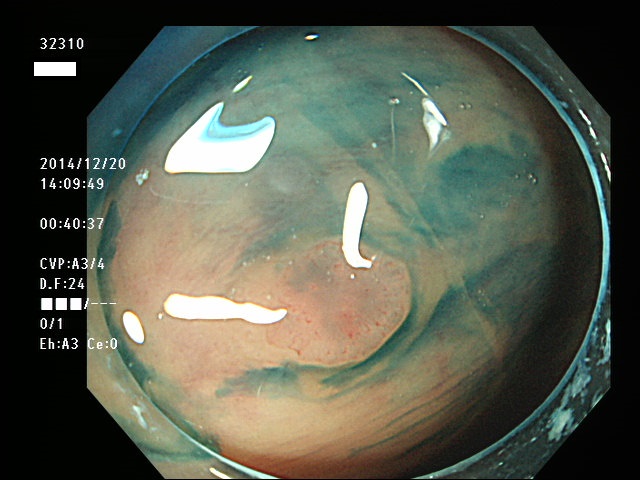

上記100名より抽出した平坦・陥凹型腺腫(=癌化の危険が高いが見落としやすい病変)の内視鏡写真